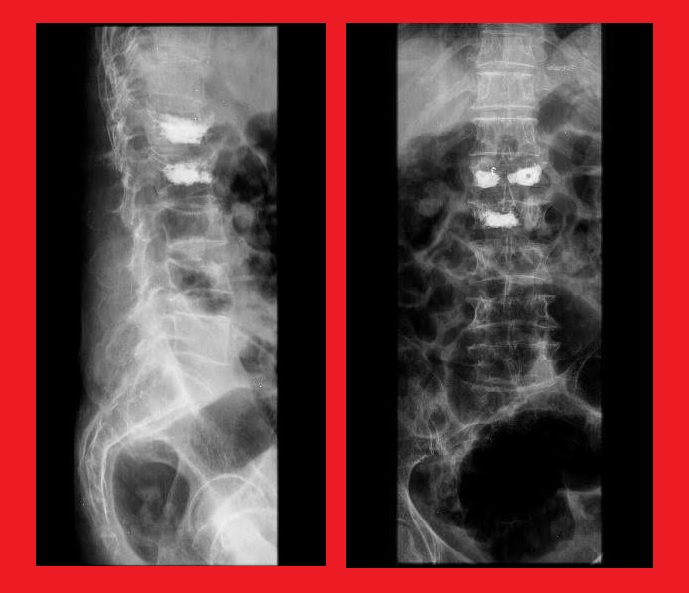

آقای ۴۵ ساله با درد شدید کمر و پای راست مراجعه کرده بودند. عکسهای بالا عکسهای قبل از عمل ایشان را نشان می دهد. همانطور که می بینید کمر قوس طبیعی ندارد و صاف می باشد (قوس کمر ۲۵ درجه و PI پنجاه و پنج درجه می باشد). عکسهای پایین عکسهای پس از عمل می باشند که با کمی کوتاه کردن پشت مهره که Ponte osteotomy نام دارد و گذاشتن کیج بین مهرهای ۴ و ۵ زاویه اصلاح شده (قوس کمر ۳۸ درجه). بیمار روز پس از عمل احساس راحتی در ایستادن و راه رفتن پیدا کرد.